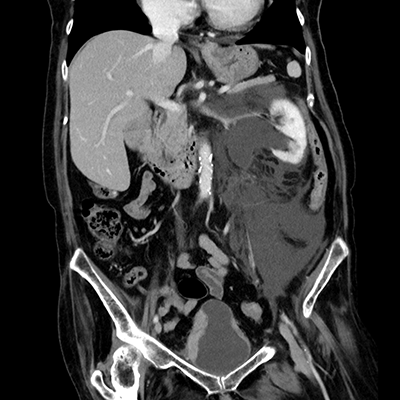

臨床画像例

中山氏 IPVは被ばく低減に役立っています。

当院では、体幹部は平均的にガイドライン*2比で50%近く低被ばくの条件で撮影していますが、読影の先生にも問題なく診断して頂いています。低被ばくに撮影することは、患者さんのメリットに繋がります。当院では、さらに患者さんに安心していただくため、被ばく線量を集計して患者さん向けの説明ツールを作っています。